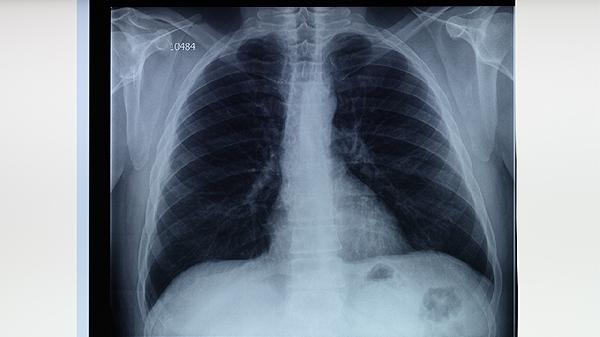

肺結(jié)核病人的常見病因主要有結(jié)核分枝桿菌感染、免疫力低下、密切接觸傳染源、居住環(huán)境擁擠、合并慢性疾病等。

結(jié)核分枝桿菌是引起肺結(jié)核的主要病原體,可通過飛沫傳播進(jìn)入人體肺部。感染后細(xì)菌在肺泡內(nèi)繁殖,導(dǎo)致肺部組織出現(xiàn)炎癥反應(yīng)和壞死。典型癥狀包括咳嗽、咳痰、低熱、盜汗等。治療需遵醫(yī)囑使用異煙肼片、利福平膠囊、吡嗪酰胺片等抗結(jié)核藥物,全程規(guī)范用藥可有效殺滅細(xì)菌。

肺結(jié)核患者應(yīng)注意保持居室通風(fēng)良好,每日開窗換氣。飲食上保證充足優(yōu)質(zhì)蛋白攝入,適量補(bǔ)充維生素A和維生素D。進(jìn)行適度有氧運(yùn)動如散步、太極拳等,避免劇烈運(yùn)動導(dǎo)致過度疲勞。嚴(yán)格遵醫(yī)囑完成全程抗結(jié)核治療,定期復(fù)查胸部影像學(xué),不可自行停藥。家庭成員中出現(xiàn)咳嗽、發(fā)熱癥狀時應(yīng)及時就醫(yī)排查。